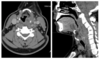

30-årig mand. Gennem fem dage symptomer han selv har tolket som halsbetændelse. Nu tilkommet feber og synkesmerter samt påvirket almen tilstand. Der er foretaget billeddiagnostisk undersøgelse (se billede).

Hvilket udsagn passer bedst ud fra anamnese og den radiologiske undersøgelse?

- a. Intet abnormt

- b. Ukompliceret højresidig tonsillit

- c. Rumopfyldende proces paratrachealt på højre side. Bør videre udredes med PET-CT

- d. Rumopfyldende proces paratrachealt på højre side, bedst forenelig med absces udgået fra tonsillit

- e. Rumopfyldende proces paratrachealt på højre side, bedst forenelig med tumor med central nekrose

(Obs! Kun ét svar skal være korrekt!)

d. Rumopfyldende proces paratrachealt på højre side, bedst forenelig med absces udgået fra tonsillit